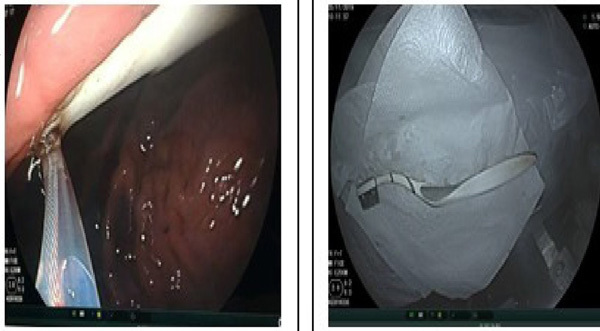

| Endoscopic image from the Hanoi Medical University Hospital. — Photo suckhoedoisong.vn |

Hanoi Medical University Hospital, who received the emergency case, said the endoscopic removal was successful in taking out the toothbrush.

Earlier in September, doctors from the northern province of Thai Nguyen said they removed an 18cm-long toothbrush from the stomach of a male patient, the outer layer of which already showed signs of being dissolved by the acidic environment during its two-week stay there.